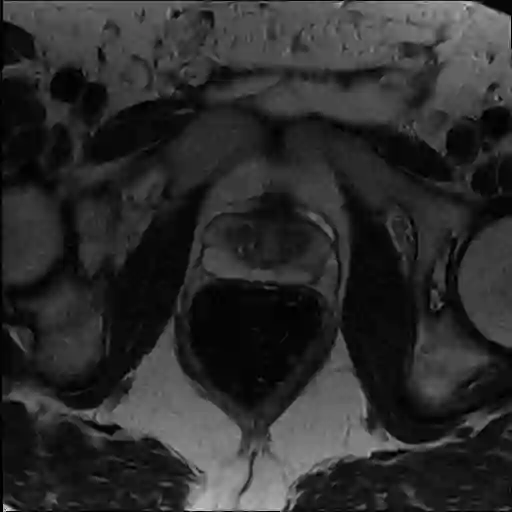

The Conditional Random Field as a Recurrent Neural Network layer is a recently proposed algorithm meant to be placed on top of an existing Fully-Convolutional Neural Network to improve the quality of semantic segmentation. In this paper, we test whether this algorithm, which was shown to improve semantic segmentation for 2D RGB images, is able to improve segmentation quality for 3D multi-modal medical images. We developed an implementation of the algorithm which works for any number of spatial dimensions, input/output image channels, and reference image channels. As far as we know this is the first publicly available implementation of this sort. We tested the algorithm with two distinct 3D medical imaging datasets, we concluded that the performance differences observed were not statistically significant. Finally, in the discussion section of the paper, we go into the reasons as to why this technique transfers poorly from natural images to medical images.

翻译:条件随机字段是一个经常性神经网络层,这是最近提出的一种算法,旨在置于现有的全进神经网络之上,以提高语义分离的质量。在本文中,我们测试这一算法是否能够改善3D多式医学图像的语义分离质量。我们开发了一个算法,该算法适用于任何空间维度、输入/输出图像频道和参考图像频道。据我们所知,这是首次可公开得到的这种类型的实施。我们用两套不同的3D医学成像数据集测试了算法,我们的结论是,观察到的性能差异在统计上没有多大意义。最后,在论文的讨论部分,我们探讨了为什么这种技术从自然图像向医学图像传播不力的原因。